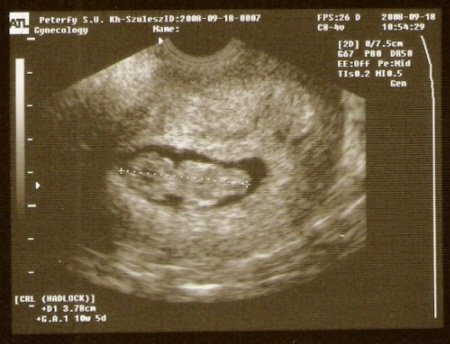

Babóval minden rendben. :D :D :D :D :D

Szabályos petezsák, egy élő embrió, CRL: 37 mm, ép testkontúrok, ábrázolódó végtagok, ritmusos szívműködés. Lepény kezdemény a mellső falon. Leválásra utaló jel nem látható.

És íme Ő:

Kép

Nagyon örülök, hogy minden rendben van és nagyon édi a picurka, én is akarok ilyet!!!!!!!!!!!!!!!!!!!!!!!!!!!!!!!!!!!!!!!!!!!!!!!!!!!!!!!!!!! :lol: :lol: :lol: :lol: :lol: :lol: :lol:

jaj,Cat,csudaszép kis pöttömöd van!És nagyon örülök, hogy minden rendben van!

Most azóta az ici-pici képet nézegetem olyan szép és olyan jól látszik a PICI :lol: :lol: :lol: :lol: :lol: :lol: :lol: :lol: :lol: :lol: